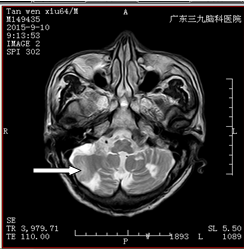

谭某,男,64岁,因反复头晕、感觉天旋地转1个多月至广东三九脑科医院治疗。

入院后,医生为其完善了所有检查,头颅MRI提示双侧小脑半球、桥脑右侧多发软化灶形成伴胶质增生、局限性脑萎缩,考虑脑梗塞后遗改变(图一);PWI-ASL提示双侧小脑半球、桥脑右侧低灌注(图二);DSA检查显示右侧颈内动脉起始部重度狭窄、狭窄程度大于90%,长 约5mm;2.右侧椎动脉开口中度狭窄,程度约45%,长约3mm,其余脑血管未见明显异常(图三)。

术前MRI(图一) 术前ASL(图二)